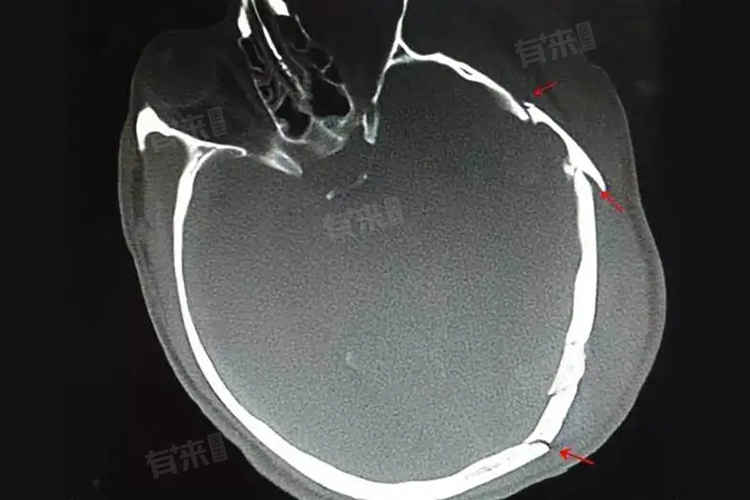

- 按骨折部位分为颅盖骨折和颅底骨折,按骨折形态分为线形骨折、凹陷骨折、粉碎骨折、洞形骨折及穿透性骨折,按骨折与外界是否相通分为开放性骨折和闭合性骨折。

- 线形骨折:多数情况下,骨折线常通过上矢状窦、横窦及脑膜血管沟,此时一般会导致颅内出血。

- 凹陷性骨折:常为接触面较小的钝器打击或头颅碰撞在凸出的物体上所致,着力点附近颅骨多全层陷入颅内,可有脑受压的症状和体征。